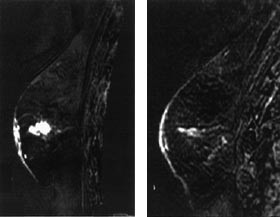

Generelt lader maligne brystkreftsvulster opp intravenøst injiserte MR-kontrastmidler raskere og kraftigere enn godartede svulster og normalt kjertelvev (fig 1). Dette har sammenheng med høyere vaskularitet og økt kapillærpermeabilitet i kreftsvulster sammenliknet med andre typer vev. Tidlige studier rapporterte at brystkreft ble diagnostisert med sensitivitet og spesifisitet på ca. 97 % når en økning i svulstens signalintensitet på 90 % eller mer i løpet av det første minuttet etter kontrastinjeksjon ble brukt som diagnostisk kriterium (11). Med økende erfaringsmateriale er det klart at også mange godartede lesjoner kan lade opp kontrastmiddel raskt og kraftig, særlig gjelder dette enkelte fibroadenomer, fibrocystisk dysplasi og skleroserende adenose (12). Spesifisiteten i senere kliniske MR-studier hvor pasientene har vært utvalgt på bakgrunn av mammografiske og kliniske funn har, avhengig av undersøkelsesteknikk og diagnostiske kriterier, variert fra 37 % til 89 % (13 – 17). Selv om enkelttilfeller av ikke-kontrastoppladende maligne brystvulster er rapportert (18), er den negative prediktive verdien av en MR-undersøkelse som ikke viser kontrastoppladende strukturer i brystet nær 100 %.

Det pågår en utstrakt forskningsaktivitet for å forbedre det diagnostiske potensialet til MR-undersøkelse av bryst. Ved MR-senteret i Trondheim har vi de siste årene særlig interessert oss for MR-teknikker som avspeiler kapillærgjennomblødningen i tumor, såkalt T2*-vektet førstepassasjebildedanning (fig 2). Bakgrunnen for å anvende denne teknikken er at kreftsvulster har flere og større kapillærer og dermed høyere kapillærperfusjon enn godartede svulster. Foreløpig synes det som om man ved denne teknikken kan påvise brystkreft med høy spesifisitet, men med en noe lavere sensitivitet enn den dynamiske T1-vektede teknikken (20). Siden T2*-vektet perfusjonsbildedanning avhenger av kapillærperfusjonen, kan metoden kanskje gi informasjon om tumorangiogenese (21) og dermed bli et hjelpemiddel både i vurderingen av kreftsvulstens metastaseringspotensial og i evalueringen av behandlingseffekten ved nye former for antitumorterapi som primært retter seg mot svulstens blodforsyning (antiangiogeneseterapi). MR-spektroskopi (MRS), hvor man benytter MR-teknikken til å få metabolsk informasjon fra svulsten, er en annen teknikk som i forskningssammenheng er brukt på brystsvulster. Metabolitten kolin, som inngår i cellemembranenes fosfolipidsyntese, er funnet i betydelige høyere konsentrasjoner i maligne enn i benigne brystsvulster, men det biokjemiske grunnlag for dette og den diagnostiske nytte av MRS i denne sammenheng trenger fortsatt evaluering (22, 23).